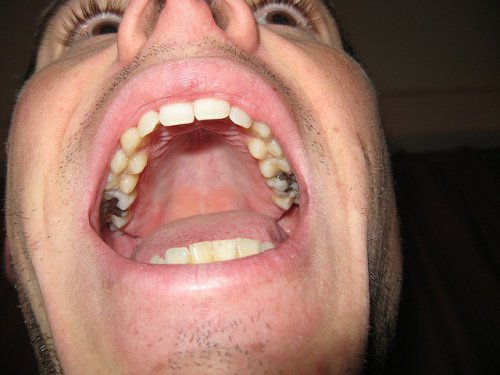

치과용 아말감 충전재가 주로 수은으로 만들어져 있으며, 이 중금속이 건강에 독이 된다는 사실을 알고 있는가? 아말감 사용이 일부 국가에서는 사용 금지되어 있다는 것도 알고 있는가?

아말감은 수은과 다양한 금속으로 만든 은색 물질로 충치로 생긴 치아 구멍을 막는데 사용한다.

아말감 충전재는 120~570mg 사이의 수은을 함유하며 침, 위산, 음식, 높은 온도 등으로 인해 시간이 지나면 천천히 빠져나온다.